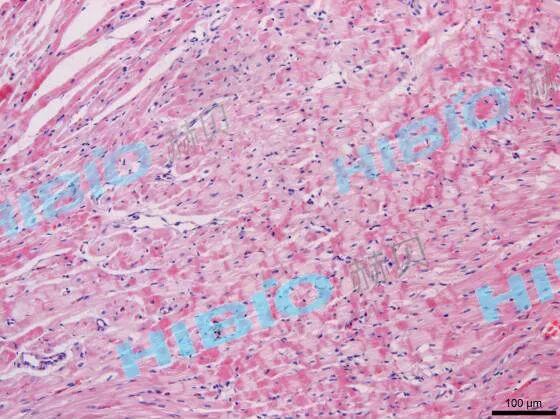

病理检查:

假手术组心肌纤维排列整齐,心肌细胞正常完整,无空泡变性、水肿;心肌间和心肌外膜无炎细胞浸润等。

模型组心肌间可见局灶性炎细胞浸润(以淋巴细胞和中性粒细胞为主),并伴随心肌外膜炎细胞浸润(以中性粒细胞为主),心肌细胞空泡变性、水肿,部分切片可见心腔内有血栓形成。

模型组 10× | 模型组 20× |